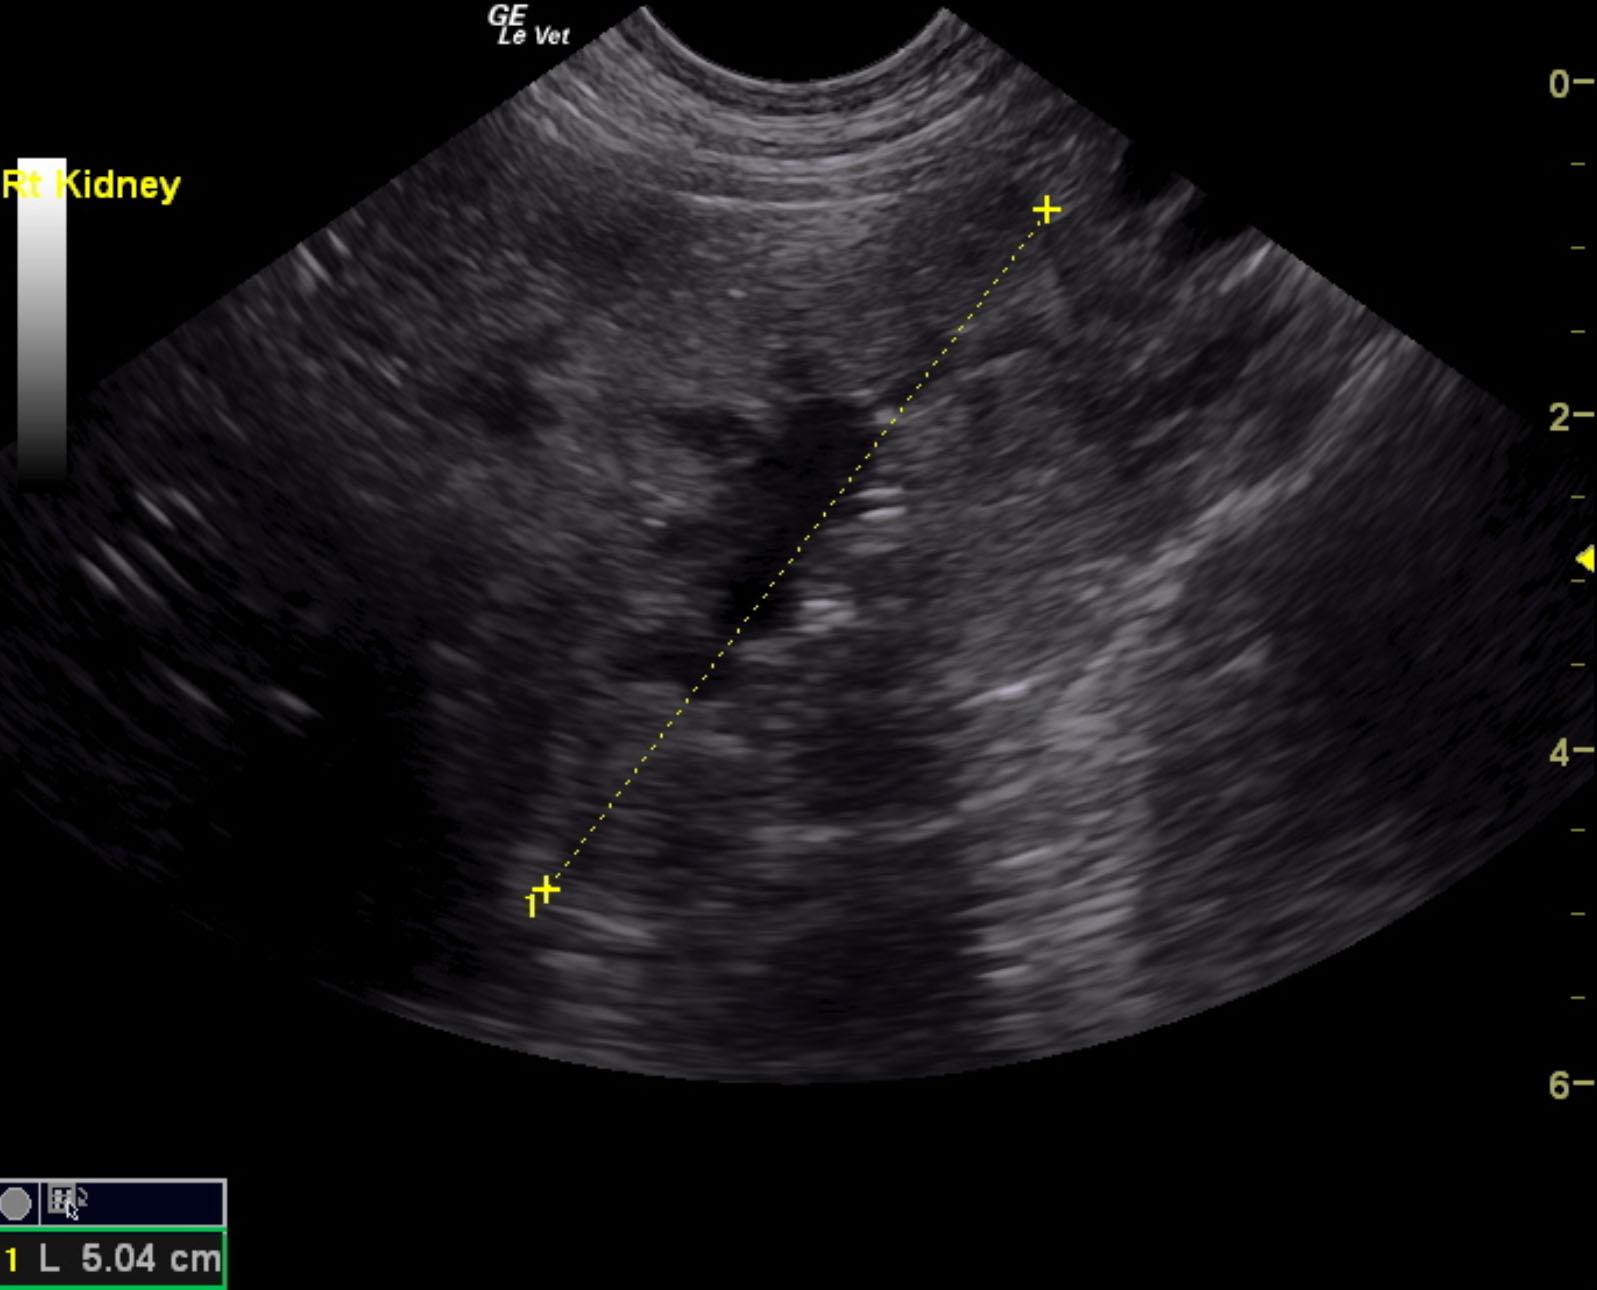

Both kidneys in this patient presented significant, dysplastic changes with cortical irregularity and disruption of the corticomedullary structure. A significant amount of microinfarctions and hyperechoic areas of mineralization and fibrosis as well as cortical cysts were noted. Color flow assessment of the renal cortices was significantly subnormal. This is consistent with chronic disease. The left kidney measured 5.08 cm. The right kidney presented pyelectasia that measured 0.76 cm. The right kidney measured 5.04 cm.